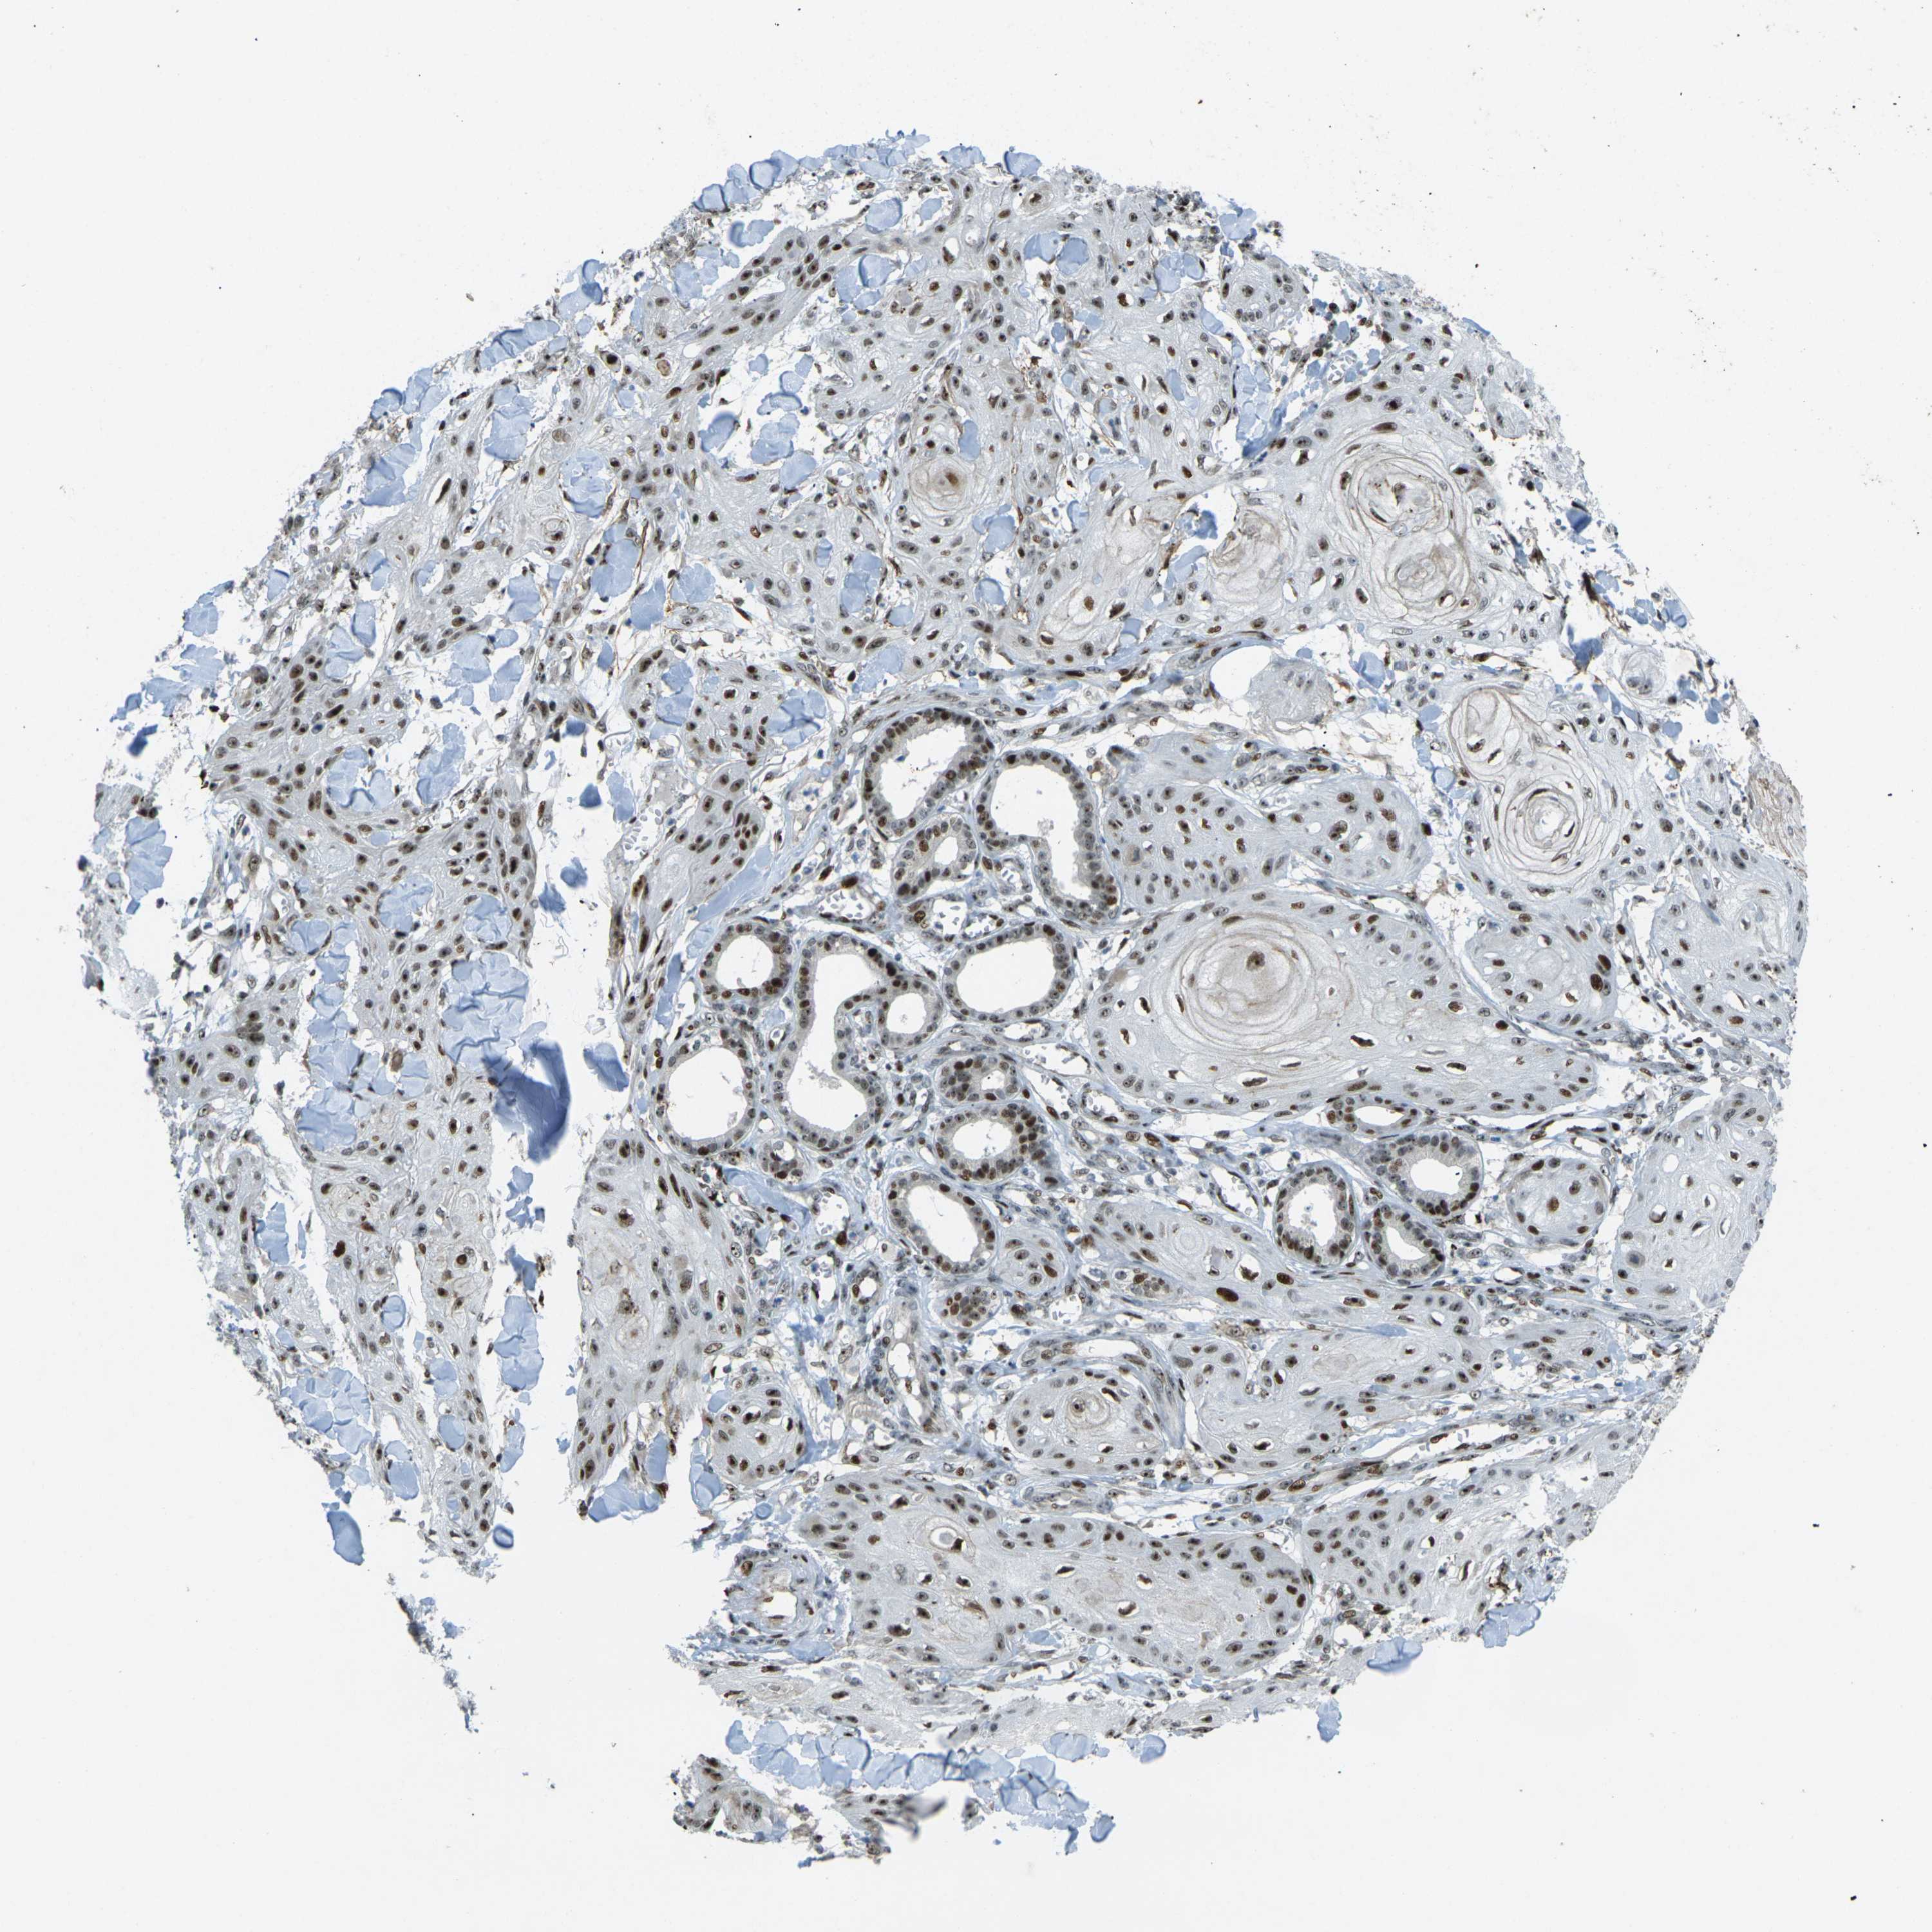

SKIN CANCER - Protein expressioni

A mouse-over function shows sample information and annotation data. Click on an image to view it in a full screen mode. Samples can be filtered based on level of antibody staining by selecting one or several of the following categories: high, medium, low and not detected. The assay and annotation is described here.

Each image is clickable and will lead to virtual microscopy that enables deeper exploration of all samples and also displays staining intensity scores, fraction scores and subcellular localization as well as patient and tissue information for each sample.

Antibody HPA054975

Antibody CAB011464

Antibody CAB035990

Antibody CAB080407

Staining

High

Medium

Low

Not detected

Location

Nuclear

Cytoplasmic/membranous

Cytoplasmic/membranous,nuclear

Squamous cell carcinoma, NOS